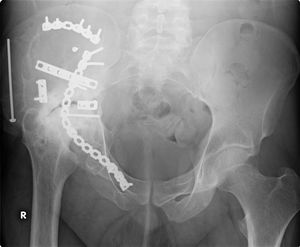

This image, taken in September 2006, shows extensive repair work to the right acetabulum 6 years after it was carried out (2000). Further damage to the joint is visible due to the onset of arthritis.